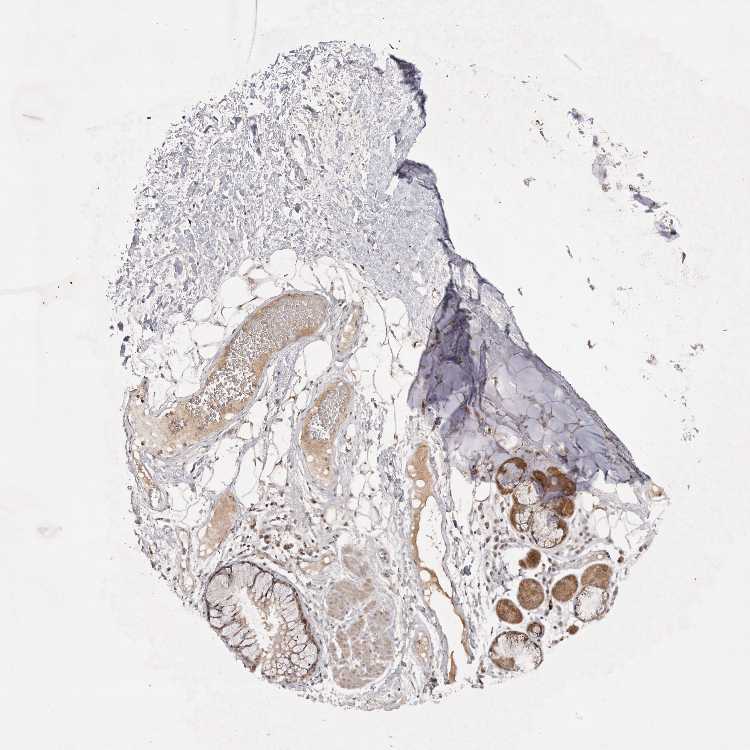

SOFT TISSUE 2 - Antibody stainingi

Antibody staining in the annotated cell types in the current human tissue is reported as not detected, low, medium, or high, based on conventional immunohistochemistry profiling in selected tissues. This score is based on the combination of the staining intensity and fraction of stained cells.

Each image is clickable and will lead to virtual microscopy that enables deeper exploration of all samples and also displays staining intensity scores, fraction scores and subcellular localization as well as patient and tissue information for each sample.

Antibody HPA025018Antibody HPA039473

Fibroblasts Not detectedHigh

Peripheral nerve Not detectedMedium